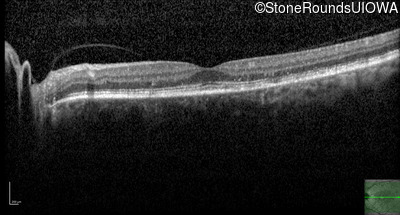

Age at visit: 59 years (Visit 3)

OD OS